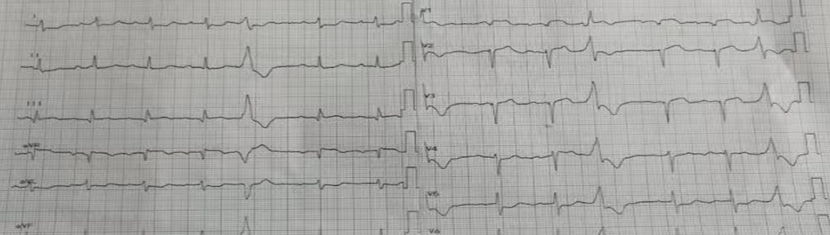

2023-04-04医联体高效联动,急性心肌梗死合并急性肺水肿休克患者重获“心”生!

2023-04-04医联体高效联动,急性心肌梗死合并急性肺水肿休克患者重获“心”生!

近日,76岁的霍大伯因胸痛前往黄埔某医院就医后,被诊断为急性心肌梗死,经胸痛联盟快速转诊前来广医五院胸痛中心救治。经过心脏中心李龙虎主任医师医护团队不懈努力的抢救和悉心照料,患者终于…